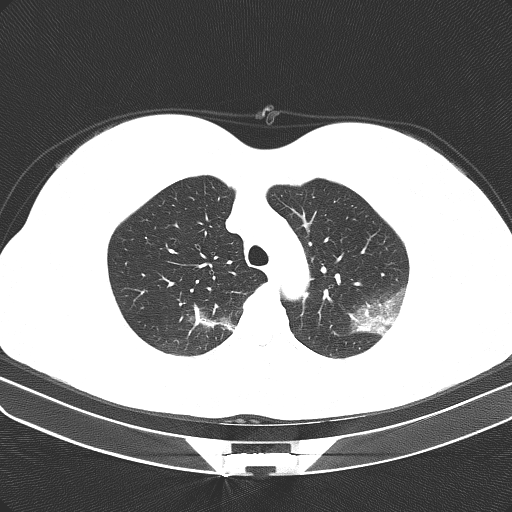

Figure 1 shows four CT scan slices, two from a non-COVID-19 CT scan, on the left and two from a COVID-19 scan, on the right. Bilateral ground glass regions are seen especially in lower lung lobes in the COVID-19 slices.

Some examples of CT slices from the cluster centers are given below. Figure 4 shows 10 consecutive slices from COVID-19 cluster center 0. Medical experts have annotated it as ’bilateral ground glass regions that appear, especially in lower lung lobes’. Figure 5 shows 10 slices from COVID-19 cluster center 2. According to medical experts’ annotation, this is consistent with ’COVID-19 pneumonia bilateral thickening filtrates’. Figure 6, on the contrary, shows 10 slices from non COVID-19 cluster center 9.